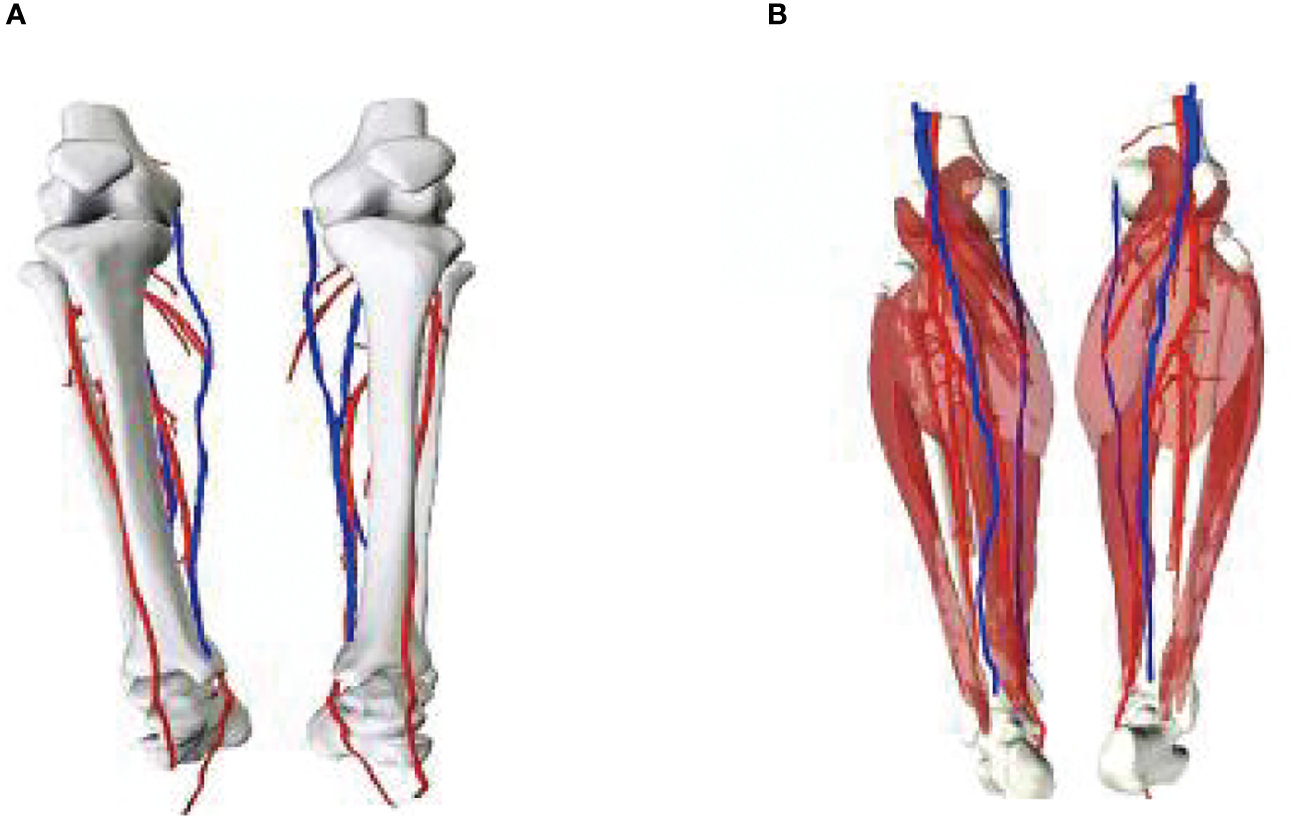

A 56-year-old female underwent surgery for ameloblastoma in the left mandible 2 years previously. Specialist examination revealed that the patient had swelling on the left face and neoplasm in the area surrounding the left mandibular angle and ramus, approximately 5.0 × 4.0 cm measuring in size. The patient also had a mild limitation in mouth opening, and 36, 37, and 38 were not detected in the oral cavity. According to the patient’s previous medical records and consultation report from the pathology department of our hospital, the pathological diagnosis of the patient was confirmed as ameloblastoma (Figure 1). The patient was diagnosed with ameloblastoma upon admission and scheduled to undergo partial mandibular resection and fibular osteocutaneous flap repair. She underwent CTA examination of the maxillofacial and the left calf prior to surgery. The obtained CTA data were imported into a software workstation for 3D reconstruction and subsequently downloaded onto a holographic display (Figures 2, 3). During the operation, the left calf was automatically positioned according to the holographic display, and the perforator vessels were dissected in real-time (Figure 4). Fibular osteocutaneous flaps were prepared to repair the mandible, and direct sutures were placed at the donor site (Figures 5, 6). After the operation, the flap fully survived, and during the 6-month follow-up, the patient expressed satisfaction with the reconstructive outcome.

Figure 3

3D models of blood vessels in lower extremities. (A) Front; (B) Posterior views of the model.